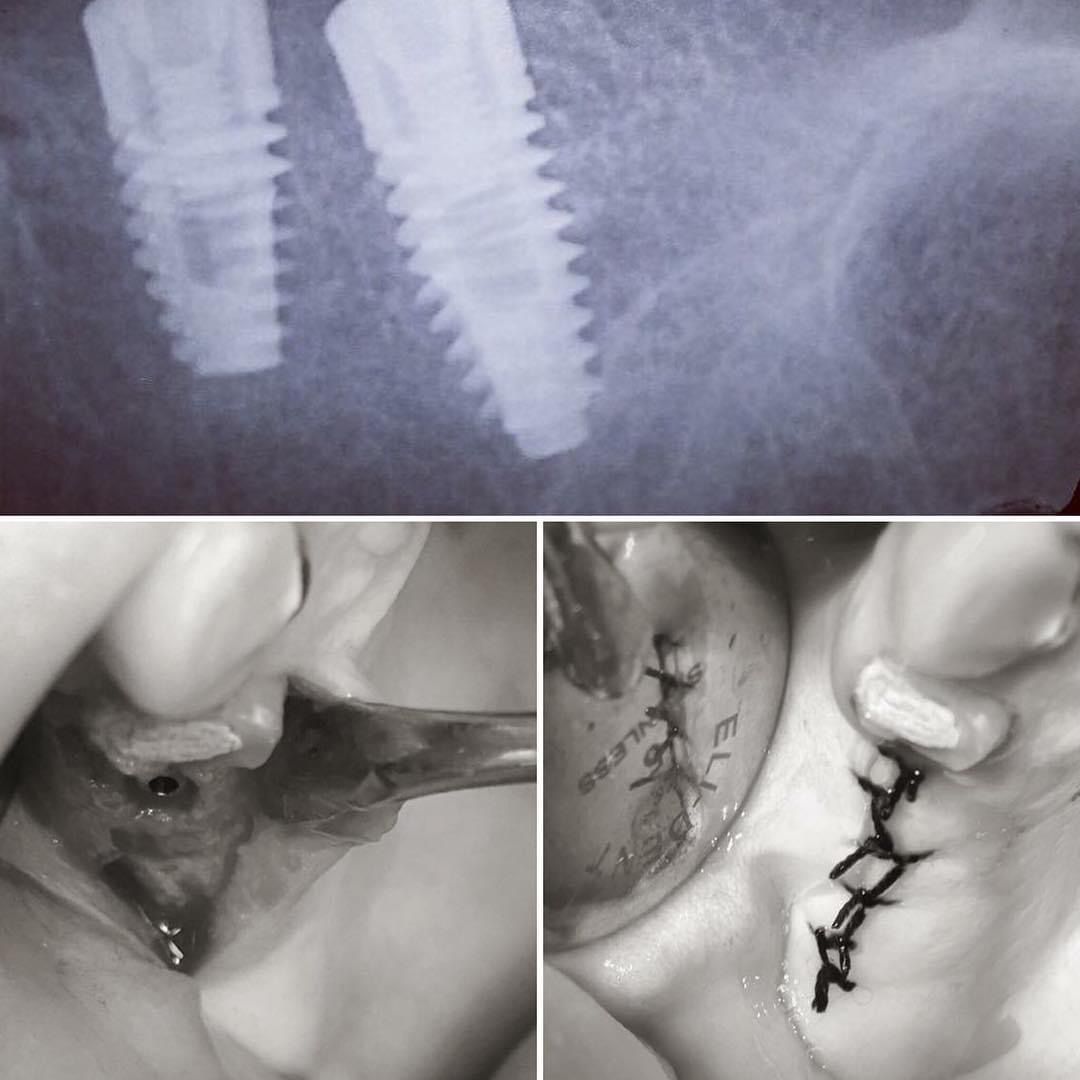

Foto e video